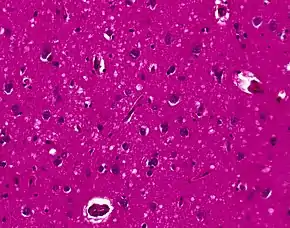

Spongiform change in CJD

Testing of tissue remains the most definitive way of confirming the diagnosis of CJD, although it must be recognized that even biopsy is not always conclusive.

In one-third of people with sporadic CJD, deposits of "prion protein (scrapie)", PrPSc, can be found in the skeletal muscle and/or the spleen. Diagnosis of vCJD can be supported by biopsy of the tonsils, which harbor significant amounts of PrPSc; however, biopsy of brain tissue is the definitive diagnostic test for all other forms of prion disease. Due to its invasiveness, biopsy will not be done if clinical suspicion is sufficiently high or low. A negative biopsy does not rule out CJD, since it may predominate in a specific part of the brain.[48]

The classic histologic appearance is spongiform change in the gray matter: the presence of many round vacuoles from one to 50 micrometers in the neuropil, in all six cortical layers in the cerebral cortex or with diffuse involvement of the cerebellar molecular layer.[49] These vacuoles appear glassy or eosinophilic and may coalesce. Neuronal loss and gliosis are also seen.[50] Plaques of amyloid-like material can be seen in the neocortex in some cases of CJD.[51]

However, extra-neuronal vacuolization can also be seen in other disease states. Diffuse cortical vacuolization occurs in Alzheimer's disease, and superficial cortical vacuolization occurs in ischemia and frontotemporal dementia. These vacuoles appear clear and punched-out. Larger vacuoles encircling neurons, vessels, and glia are a possible processing artifact.[48]